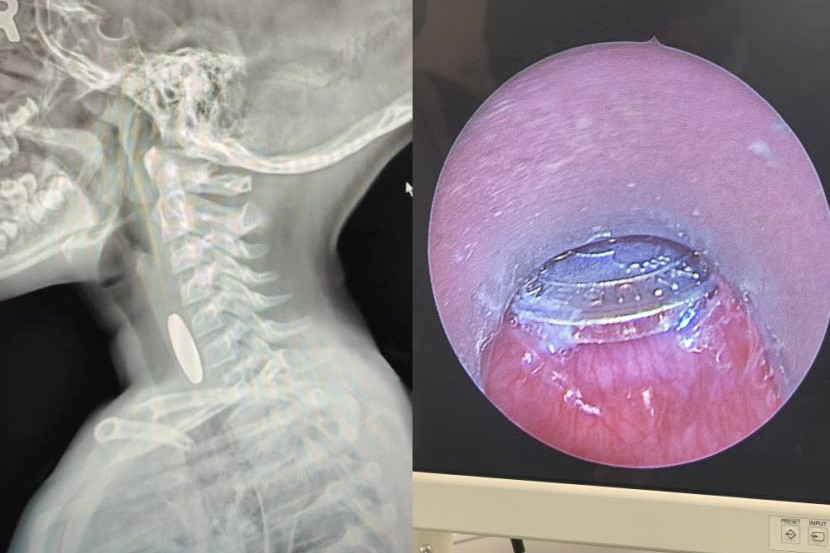

Token mesin permainan yang berjaya dikeluarkan.

Ujar doktor tersebut, hasil imbasan x-ray menunjukkan sesuatu seperti sekeping duit syiling yang tersekat pada saluran esophagus kanak-kanak berkenaan.

Namun selepas diteliti dan prosedur pembedahan dilakukan, doktor tersebut terkejut apabila mendapati bendasing tersebut rupanya sekeping token mesin permainan.

"Apabila dah sampai ke bahagian atas esofagus ini, tak rupa macam duit syiling. Dalam hati... apa benda pula kalau bukan syiling ni.

"Rupanya bukan duit syiling tapi token games yang berjaya dikeluarkan. Untuk rekod, ini kali pertama saya mendapat kes sebegini.